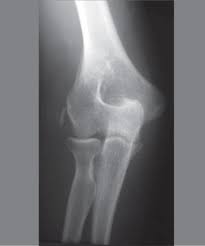

The common extensor tendon attaches to the lateral epicondyle, acting as the common attachment for the superficial extensor muscles of the forearm. The lateral epicondyle of the humerus is a large, tuberculated eminence, curved a little forward, and giving attachment to the radial collateral ligament of the elbow joint, and to a tendon common to the origin of the supinator and some of the extensor muscles. Tennis elbow assessment explore the. Related online courses on physioplus. Lateral epicondylitis is defined as a pathologic condition of the wrist extensor muscles at their origin on the lateral humeral epicondyle. This area can become tender to the touch. Pain is felt over the lateral epicondyle and radiates down forearm. Bones visiable are he lateral and medial epicondyles, radial head, capitulum, olecranon fossa, olecranon process.

Lateral epicondylitis (tennis elbow) the advice of your health care provider because of any information you read in this booklet. Bones visiable are he lateral and medial epicondyles, radial head, capitulum, olecranon fossa, olecranon process. Pain upon resisted wrist extension. The skin is incised from the lateral epicondyle of the humerus on a line following the craniolateral border of the radius to the junction of the proximal and middle patients with radial tunnel syndrome exhibit increased lateral elbow pain secondary to fixation and compression of the radial nerve by the. Resisted wrist extension with elbow fully extended.